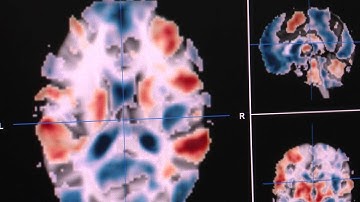

Russell Poldrack - “From Reverse Inference to Pattern Classification”